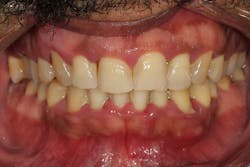

- 50% of the cases are typically attributed to phenytoin (figure 3).

- 10% to 20% of the cases are typically attributed to calcium channel blockers, with nifedipine being the most notable problem (figures 4a and 4b).